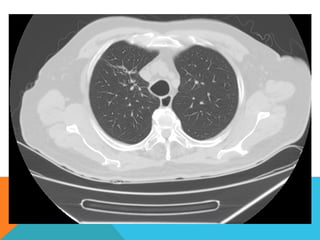

ABORDAJE TÉCNICO: Serealiza estudio con ventana mediastinal y de parénquima pulmonar con técnica de ALTA RESOLUCION, en inspiración y espiración, mediante  cortes axiales, desde ápices hasta bases pulmonares, con las siguientes observaciones En las partes blandas y las estructuras óseas dentro de los límites de la normalidad. Las regiones axilares libres. Ambos pulmones con neumatización conservada, con sobredistensión pulmonar, y áreas de atrapamiento aéreo, bilateral con cambios fibrosos cicatriciales apicales derechos. Se demuestran áreas de condensación en topografía predominantemente parenquimatosa pulmonar derecha, la mayor de ellas evidenciada hacia la base, acompañada de broncograma aéreo, la medición máxima al corte axial de 6.1 por 2.2 cm, en topografía del segmento posterior del lóbulo inferior, S10 así como también otra más se definen topografía de similares características en topografía del segmento medial del lóbulo medio, S5. En topografía parenquimatosa pulmonar izquierda imagen de similares características a las ya descritas en topografía del segmento lingular inferior, S4. No hay derrame ni áreas de engrosamiento pleurales. El patrón vascular es de características normales donde no se delimitan imágenes de lesiones aneurismáticas únicamente cambios por aortoesclerosis incipiente. El corazón de dimensiones conservada, de contornos regulares, sin desplazamientos; en la región hiliar derecha se define adenopatía de medición máxima corte axial de 1.6 por 1.4 cm.

En los cortesrealizados hacia las bases pulmonares es posible delimitar los órganos sólidos intraabdominales tales como el hígado sin anormalidades que consignar; se demuestra imagen hiperdensa puntiforme en topografía del parénquima esplénico en relación a calcificación inespecífica. Hay distensión aérea esofágica que lo define prácticamente su totalidad. Se demuestran imágenes hiperdensas en topografía intraluminal vesicular que corresponden con colelitiasis. Se define imagen hipodensa parenquimatosa renal superior derecha con patrón de atenuación homogéneo, líquido que condiciona la sospecha de lesión focal benigna tipo quística simple. INTERPRETACIÓN DIAGNÓSTICA:   ESTUDIO ANORMAL QUE DEMUESTRA HALLAZGO INESPECIFICO DE SOBREDISTENSIÓN PULMONAR  CON CAMBIOS FIBROSOS CICATRICIALES APICALES DERECHOS Y ÁREAS DE CONDENSACIÓN PARENQUIMATOSAS PULMONARES, DE PREDOMINIO DERECHO, LA DE MAYORES DIMENSIONES BASAL DERECHA, ASOCIADA CON BRONCOGRAMA AÉREO. COLELITIASIS.

El estudio radiológicosimple evidencia una lesión nodular menor del centímetro, radiodensa, caracterizada como granuloma cálcico. En mi opinión el estudio de TCAR fue realizado por ese motivo y ello permito identificar los hallazgos “floridos” que ya se señalan y se muestran en las imagen axiales ya seleccionadas.